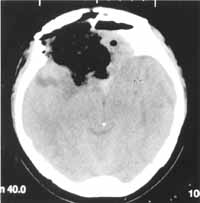

锁孔手术应注意其适应证的掌握,肿瘤的大小不是手术的绝对适应证或禁忌证,决定是否采用小切口技术主要是看肿瘤的血液供应情况[5]。本组切除的肿瘤最大径达12cm,其中有脑膜瘤(最大径8cm,见图1、图2)、听神经瘤和胶质瘤,只要肿瘤供血不是十分丰富,手术可以顺利完成。

图2 经额锁孔手术完全切除肿瘤后7天CT,肿瘤完全消失